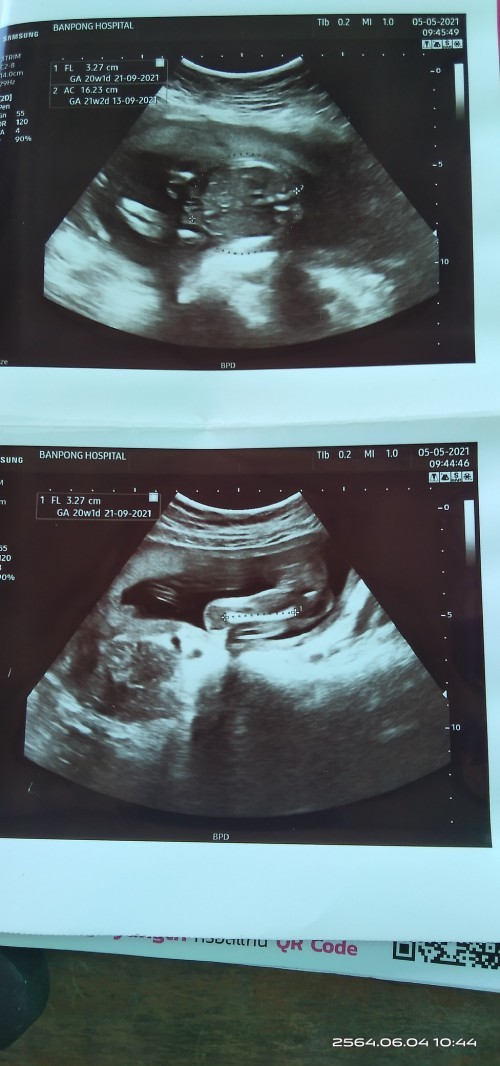

แม่! 🤰💖อวดรูปอัลตร้าซาวด์กัน

โชว์รูปแรกของเบบี้กันหน่อยน้า เพศหญิง👧หรือชาย🧑เอ่ยยย 😍🥰💜 17/09/2563